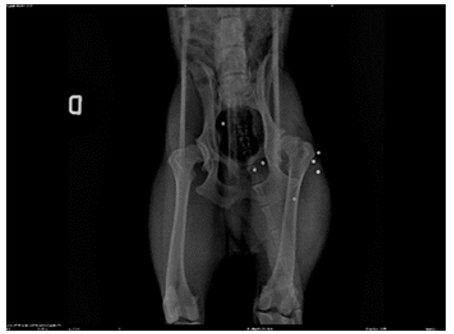

Figure 2: Pre-Surgery X-ray (Lateral Position) Showing Bilateral Coxofemoral Dysplasia and the Presence of Metallic Artifacts (Lead Pellets from a Firearm with which the Animal was Unfortunately Shot)

In Figures 2 and 3, we observe the bilateral coxofemoral joint in a ventrodorsally and lateraly view, where severe bilateral coxofemoral joint incongruence is noted, with evident femoral head luxation in the left limb. The presence of osteophytes along the acetabular margins and bilateral atrophy of the thigh muscles are also observed. In Figure 4, the absence of the coxofemoral joint is evident, showing the radiograph following the second surgery, where bilateral ostectomy was performed. The presence of acetabular osteophytes and bilateral atrophy of the thigh muscles is highlighted

The canine was discovered abandoned near the municipal kennel and subsequently rescued. Following a medical examination and X-rays, the dog was diagnosed with severe coxofemoral dysplasia, necessitating femoral head ostectomy due to joint dislocation (Figures 2 and 3). The initial surgery took place in March 2022 the left limb followed by a subsequent procedure in August 2022. (figure4)for the rigth limb.